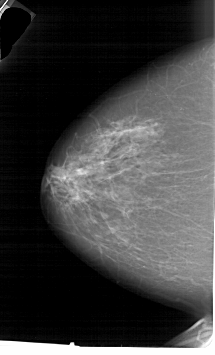

A_1646_1.LEFT_CC

LEFT_CC LINES 6376 PIXELS_PER_LINE 3856 BITS_PER_PIXEL 12 RESOLUTION 43.5 NON_OVERLAY